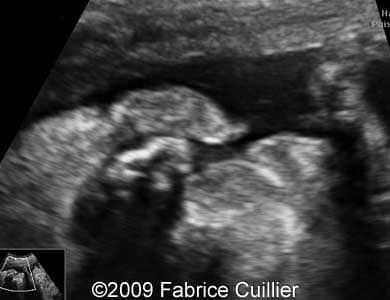

The following images show a case of an unilateral cleft lip diagnosed at 25 weeks old fetus of a 22-year-old mother with non-contributive history. No other anomaly was found. Karyotyping revealed normal karyotype (46,XX) and the course of the pregnancy was uneventful. The neonate was delivered at 38 weeks and its surgery is scheduled at six months.

Images 1, 2, 3: 2D images showing unilateral cleft lip.